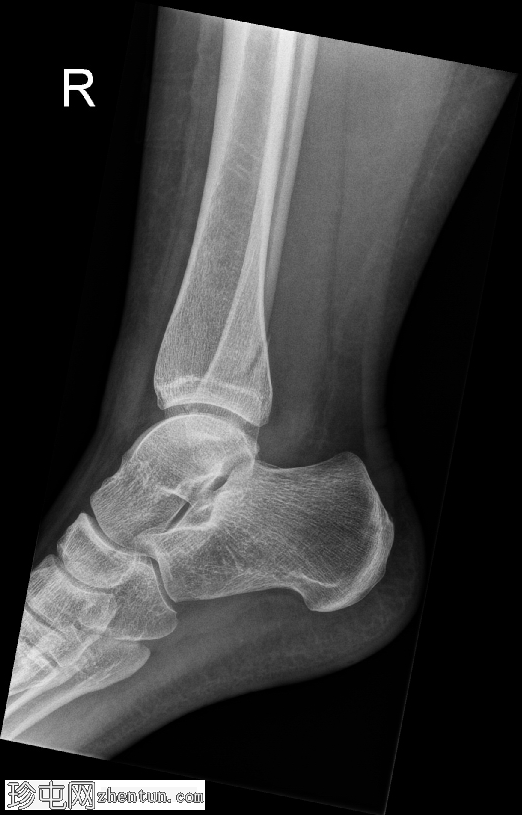

侧位片

腓骨远端在胫腓联合水平处发生螺旋形骨折,符合Weber B型骨折。远端骨折块轻度向外侧移位。距骨在踝关节内也出现向外侧移位。

内侧胫距关节间隙增宽,胫腓骨重叠减少,胫腓间隙增宽。这些发现提示胫腓联合韧带损伤,并提示踝关节不稳。可见轻度软组织肿胀。